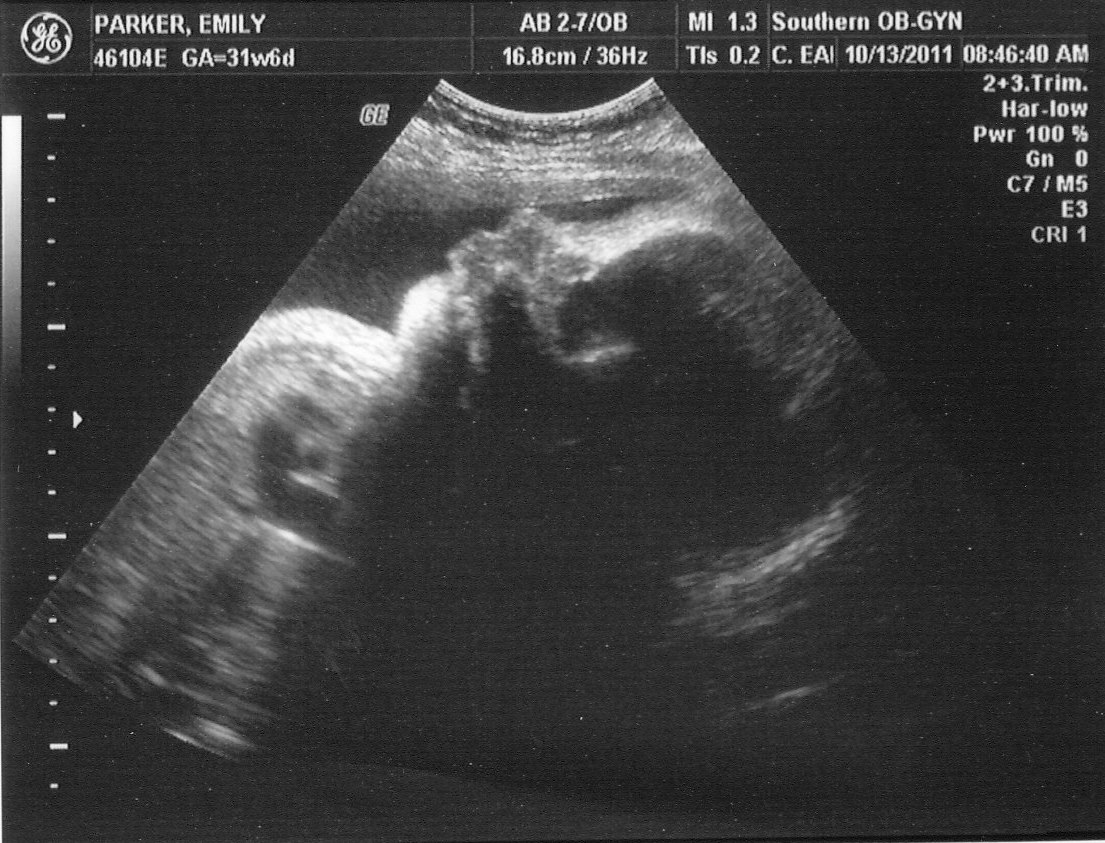

Acerca de 32 Week OBGYN Visit ~ Last Ultrasound! - The Journey of Parenthood...

Days of our lives...: 32 weeks Ultrasound viral